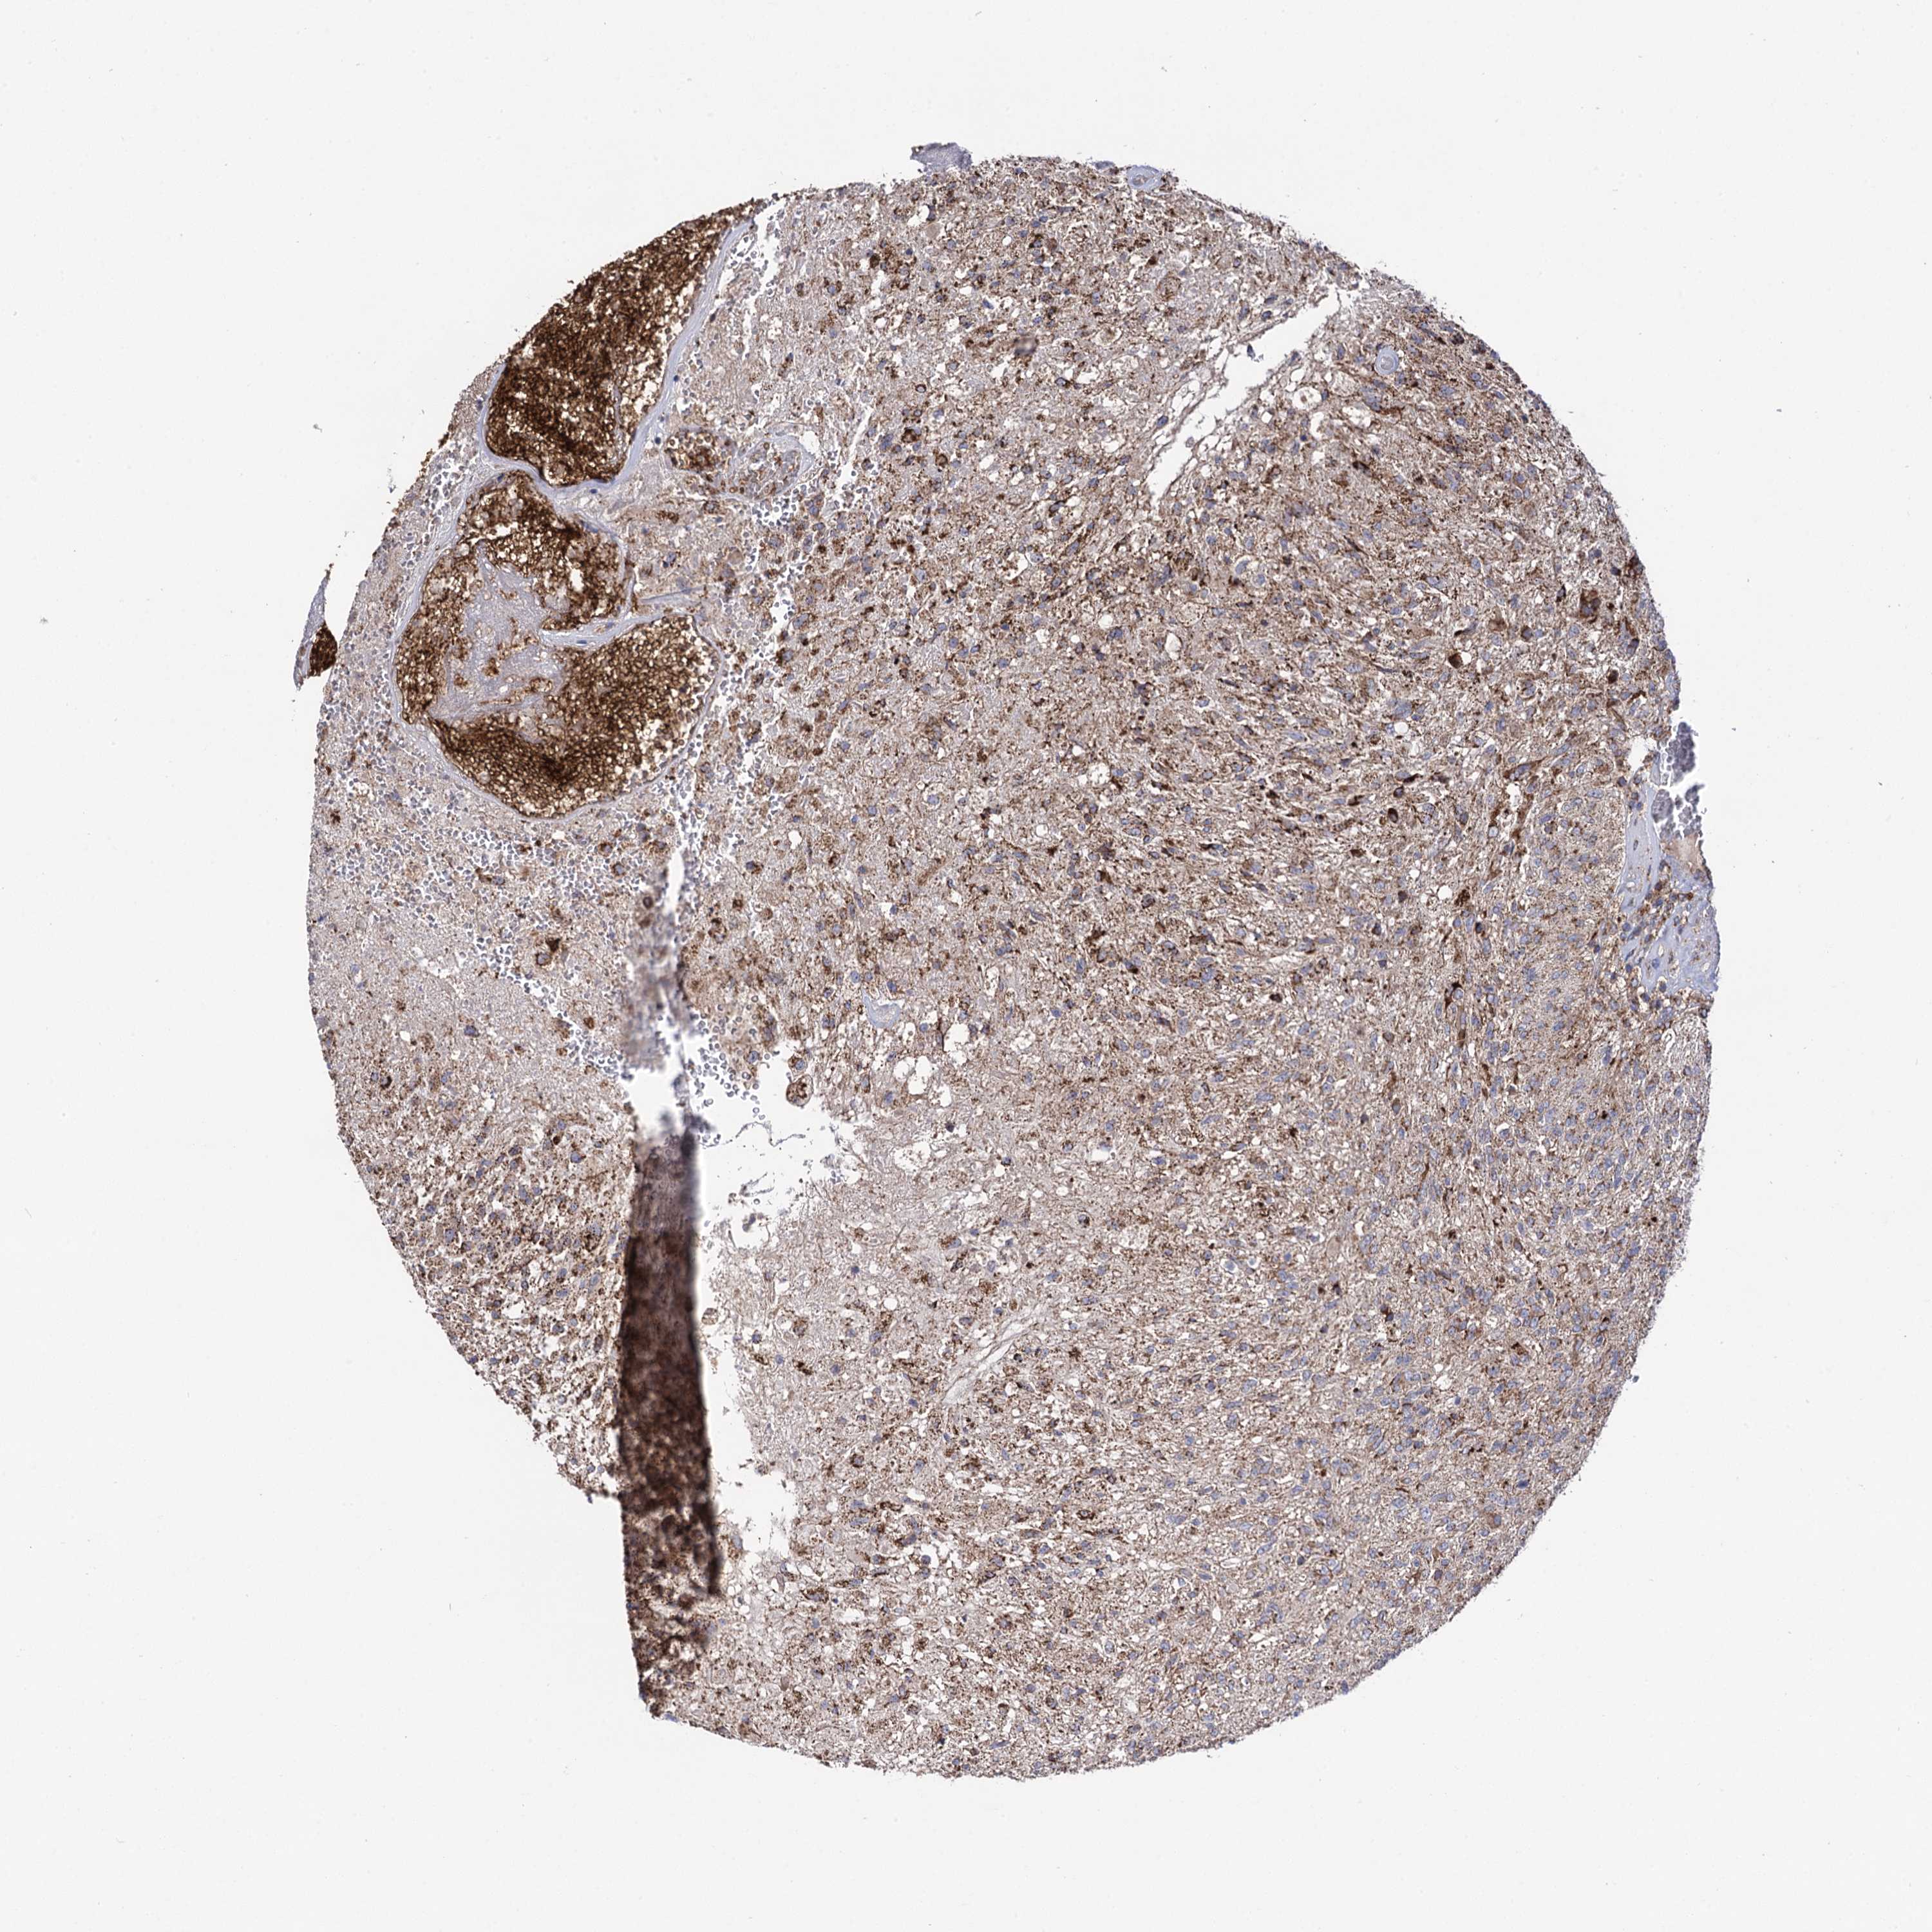

GLIOMA - Protein expressioni

A mouse-over function shows sample information and annotation data. Click on an image to view it in a full screen mode. Samples can be filtered based on level of antibody staining by selecting one or several of the following categories: high, medium, low and not detected. The assay and annotation is described here.

Note that samples used for immunohistochemistry by the Human Protein Atlas do not correspond to samples in the TCGA dataset.

Antibody stainingi

Antibody staining in the annotated cell types in the current human tissue is reported as not detected, low, medium, or high, based on conventional immunohistochemistry profiling in selected tissues. This score is based on the combination of the staining intensity and fraction of stained cells.

Each image is clickable and will lead to virtual microscopy that enables deeper exploration of all samples and also displays staining intensity scores, fraction scores and subcellular localization as well as patient and tissue information for each sample.

Antibody HPA040845

Staining

High

Medium

Low

Not detected

Intensity

Strong

Moderate

Weak

Negative

Quantity

>75%

75%-25%

<25%

None

Location

Nuclear

Cytoplasmic/membranous

Cytoplasmic/membranous,nuclear

Glioma, malignant, High grade

Glioma, malignant, Low grade